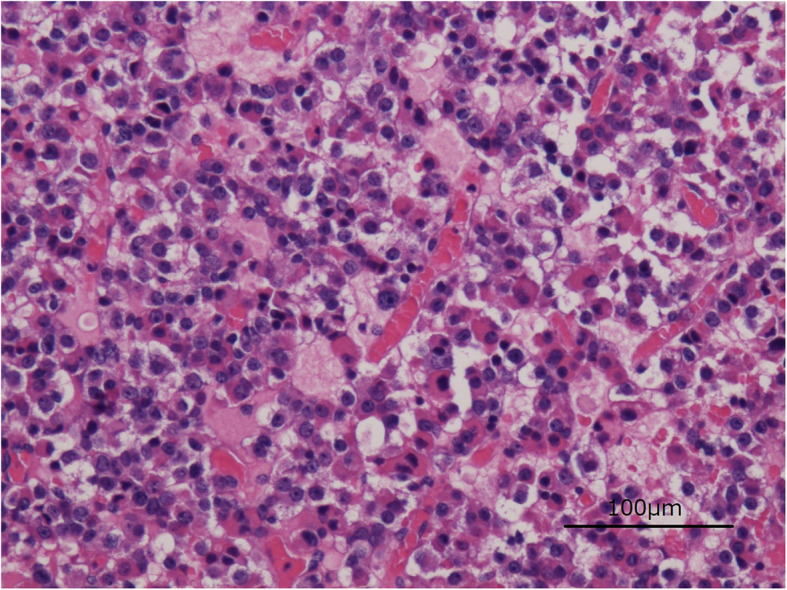

On the third day after the operation, rehabilitation was started with a cervical collar and hard thoracolumbar corset. The postoperative course was good, the paralysis gradually improved, and the patient was able to walk alone indoors. She was discharged 3 weeks after the operation. There have been no adverse or unanticipated events. Two months after the spinal surgery, resection of the pituitary adenoma was performed in the neurosurgery department, and the patient is still under observation. A pathological image (H&E, × 400) is provided and showed a sheet of monotonous cells with round nuclei and loss of normal lobular patterns of the pituitary adenoma (Fig. 6). Staining for TSH and ACTH was negative. Staining for PRL was positive in 10% of the resected pituitary tissue. Staining for CAM5.2 was diffusely positive in many cells and several cells had fibrous bodies. These findings are consistent with growth hormone-secreting pituitary adenomas. We did not have other antibodies, so it was difficult to classify the pituitary adenoma in detail.

Fig. 6.

Pathological image of a pituitary adenoma (H&E, × 400). A sheet of monotonous cells with round nuclei and loss of normal lobular patterns of the pituitary adenoma. Using a microscope (BX51, Olympus, Tokyo, Japan) and an objective lens of × 20, the figure was taken under the settings of 1280 × 960 pixel (Camera, DS-F1, Nikon, Tokyo, Japan; Detector, Digital Sight DS-L2, Nikon, Tokyo, Japan)